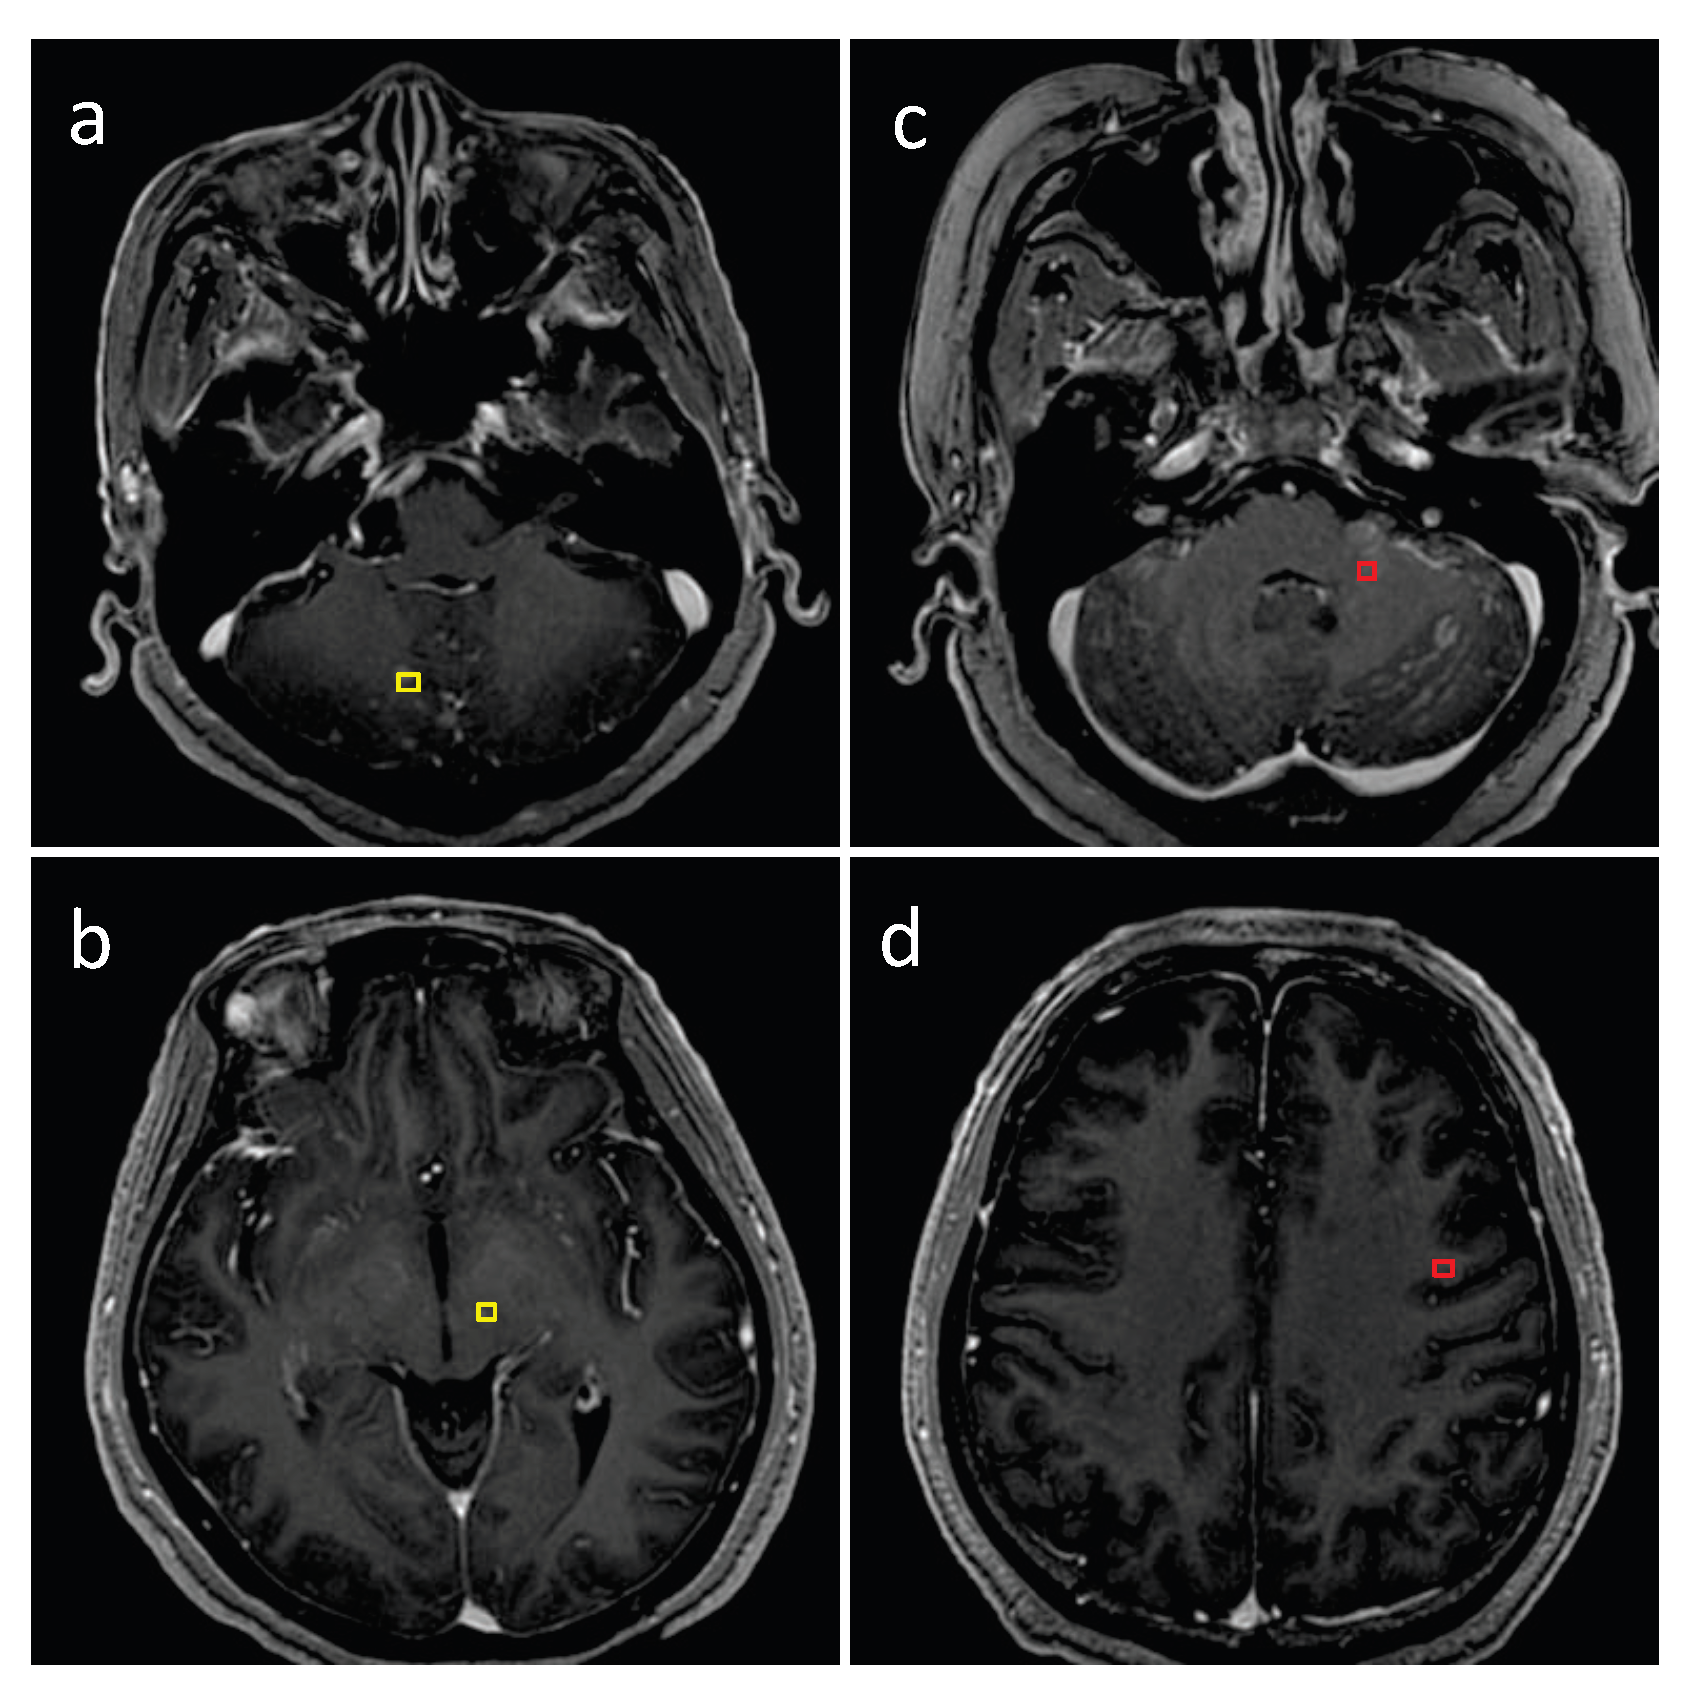

3.1. Detection Performance of SA-YOLOv5

3.4. Detection Performance on the External Testing Set